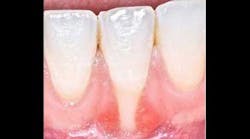

Gingival recession is defined as “the migration of the marginal soft tissue apical to the cementoenamel junction” (CEJ). Histologically, the destruction is associated with the loss of periodontal connective tissue fibers and alveolar bone, leading to exposure of the root surface to the oral environment. (3)This loss of hard- and soft-tissue-supporting structures ultimately increases the probability that patients will experience thermal or tactile sensitivity, esthetic concerns, and an increased susceptibility for root caries.

According to the proceedings from the 2014 American Academy of Periodontology Regeneration Workshop, root coverage may be attained through the application of a variety of surgical procedures. These outcomes are generally measured by reduced defect depth, gain in clinical attachment, and an increase in keratinized tissue. The associated systematic reviewprovides clear evidence that a subepithelial connective tissue graft (SCTG) procedure offers the best outcome for mean and complete root coverage, as well as an increase in keratinized tissue. (4,5) Strong evidence also supports biomaterials such as acelullar dermal matrix grafts (ADMG) or enamel matrix derivative (EMD) in conjunction with a coronally advanced flap (CAF) that can be used as an alternative to treat Miller Class I and II single-tooth gingival recession defects (figures 1 and 2). (6)Another suggestion from the proceedings was that using a split-thickness flap or tunnel technique can help to revascularize the graft by maintaining an excellent vascular supply to the flap.